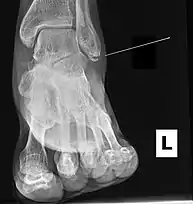

Ankle radiographs are used to detect widening of the tibiofibular syndesmosis or medial clear space. The medial clear space is the area between the talus of the ankle and the medial malleolus. Damage to the deltoid ligament and syndesmotic ligaments result in mortise instability, causing the talus to laterally shift and widen the medial clear space.[4][12] A clinical study, conducted in 2006 and published in the Journal of Bone and Joint Surgery, found that the medial clear space size of a normal ankle and an injured ankle measured at 4 millimetres and 5.4 millimetres in length respectively.[11] To confirm diagnosis, full-leg radiographs are used to inspect for fractures of the proximal fibula and widening of the interosseous clear space (or tibiofibular clear space). The interosseous clear space is the area between the medial side of the fibula and lateral side of the tibia. A peer-reviewed study, published in Injury in 2004, found that an interosseous clear space greater than 10 millimetres indicates diastasis of the syndesmotic ligaments.[4]

If necessary, Computed Tomography (CT) or Magnetic Resonance Imaging (MRI) may also be used to clarify diagnosis. MRI scans can check for interosseous membrane or tibial tubercle damage if high instability of the ankle is diagnosed.[8][11] Arthroscopy may be used to diagnose a syndesmotic lesion but is often not recommended due to operative difficulty.[13] Stress radiographs of the ankle are used to assess the integrity of the deltoid ligament and tibiofibular syndesmosis.[9][13] The size of the medial clear space can also be measured using stress radiography.[11]

X-ray, CT, or MRI scans can be used to diagnose the extent of the Maisonneuve fracture's damage and determine whether it is a simple or comminution fracture.[8] During diagnosis, a supination-external rotation pattern of injury may also be concluded if there is an isolated fracture of the posterior tubercle of the tibia.[9]